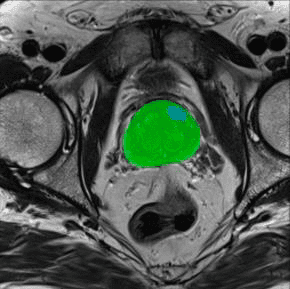

The challenge is partly mechanical. A biopsy needle must be hand-guided through soft tissue to hit a walnut-sized target that’s often nearly invisible on MRI scans. The procedure is delicate, requiring skill and experience. Tiny tumours are easily missed, and the patient goes home relieved, unaware that a malignancy may still be present.

This is where robots re-enter the story. Paolo’s idea was simple: automate prostate biopsy so the needle hits exactly where the scan says it should. The team built a prototype and validated the concept with support from the European Research Council Proof of Concept PROST initiative. “We made a first prototype, published it, and doctors responded enthusiastically: ‘Yes, do it – this is interesting,’” Paolo recalls.